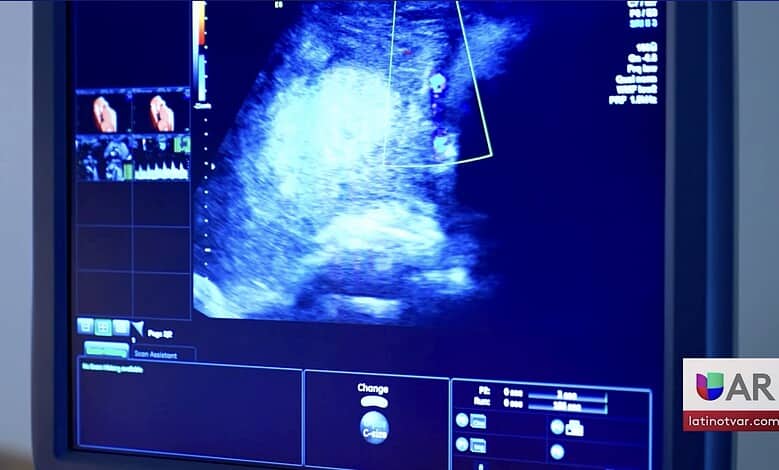

Entre los casos citados se incluyen embarazos de alto riesgo, condiciones fetales fatales y embarazos producto de agresión sexual, lo que obligó a las pacientes a buscar abortos en otros estados.